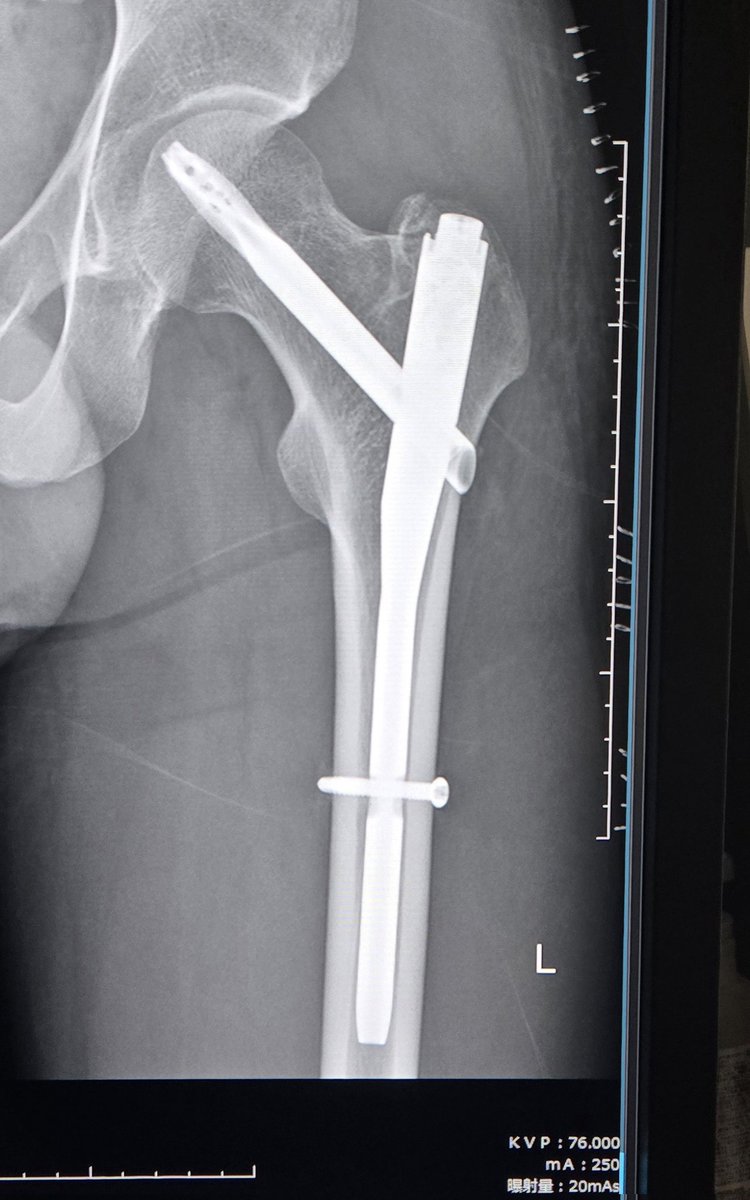

【大腿骨転子部骨折 14日目】 無事に帰国し、今日は骨の確認と医療用ホッチキスを外してもらった! 自分の身体には、こんなに大きなチタン製のスクリューが入っている🔩 骨が治ったら抜いて、チタンブルーにしてオブジェにしようと考えていたが、基本的には一生入れたままらしい😂 リハビリも順調!

【大腿骨転子部骨折 14日目】

無事に帰国し、今日は骨の確認と医療用ホッチキスを外してもらった!

自分の身体には、こんなに大きなチタン製のスクリューが入っている🔩

骨が治ったら抜いて、チタンブルーにしてオブジェにしようと考えていたが、基本的には一生入れたままらしい😂

リハビリも順調!